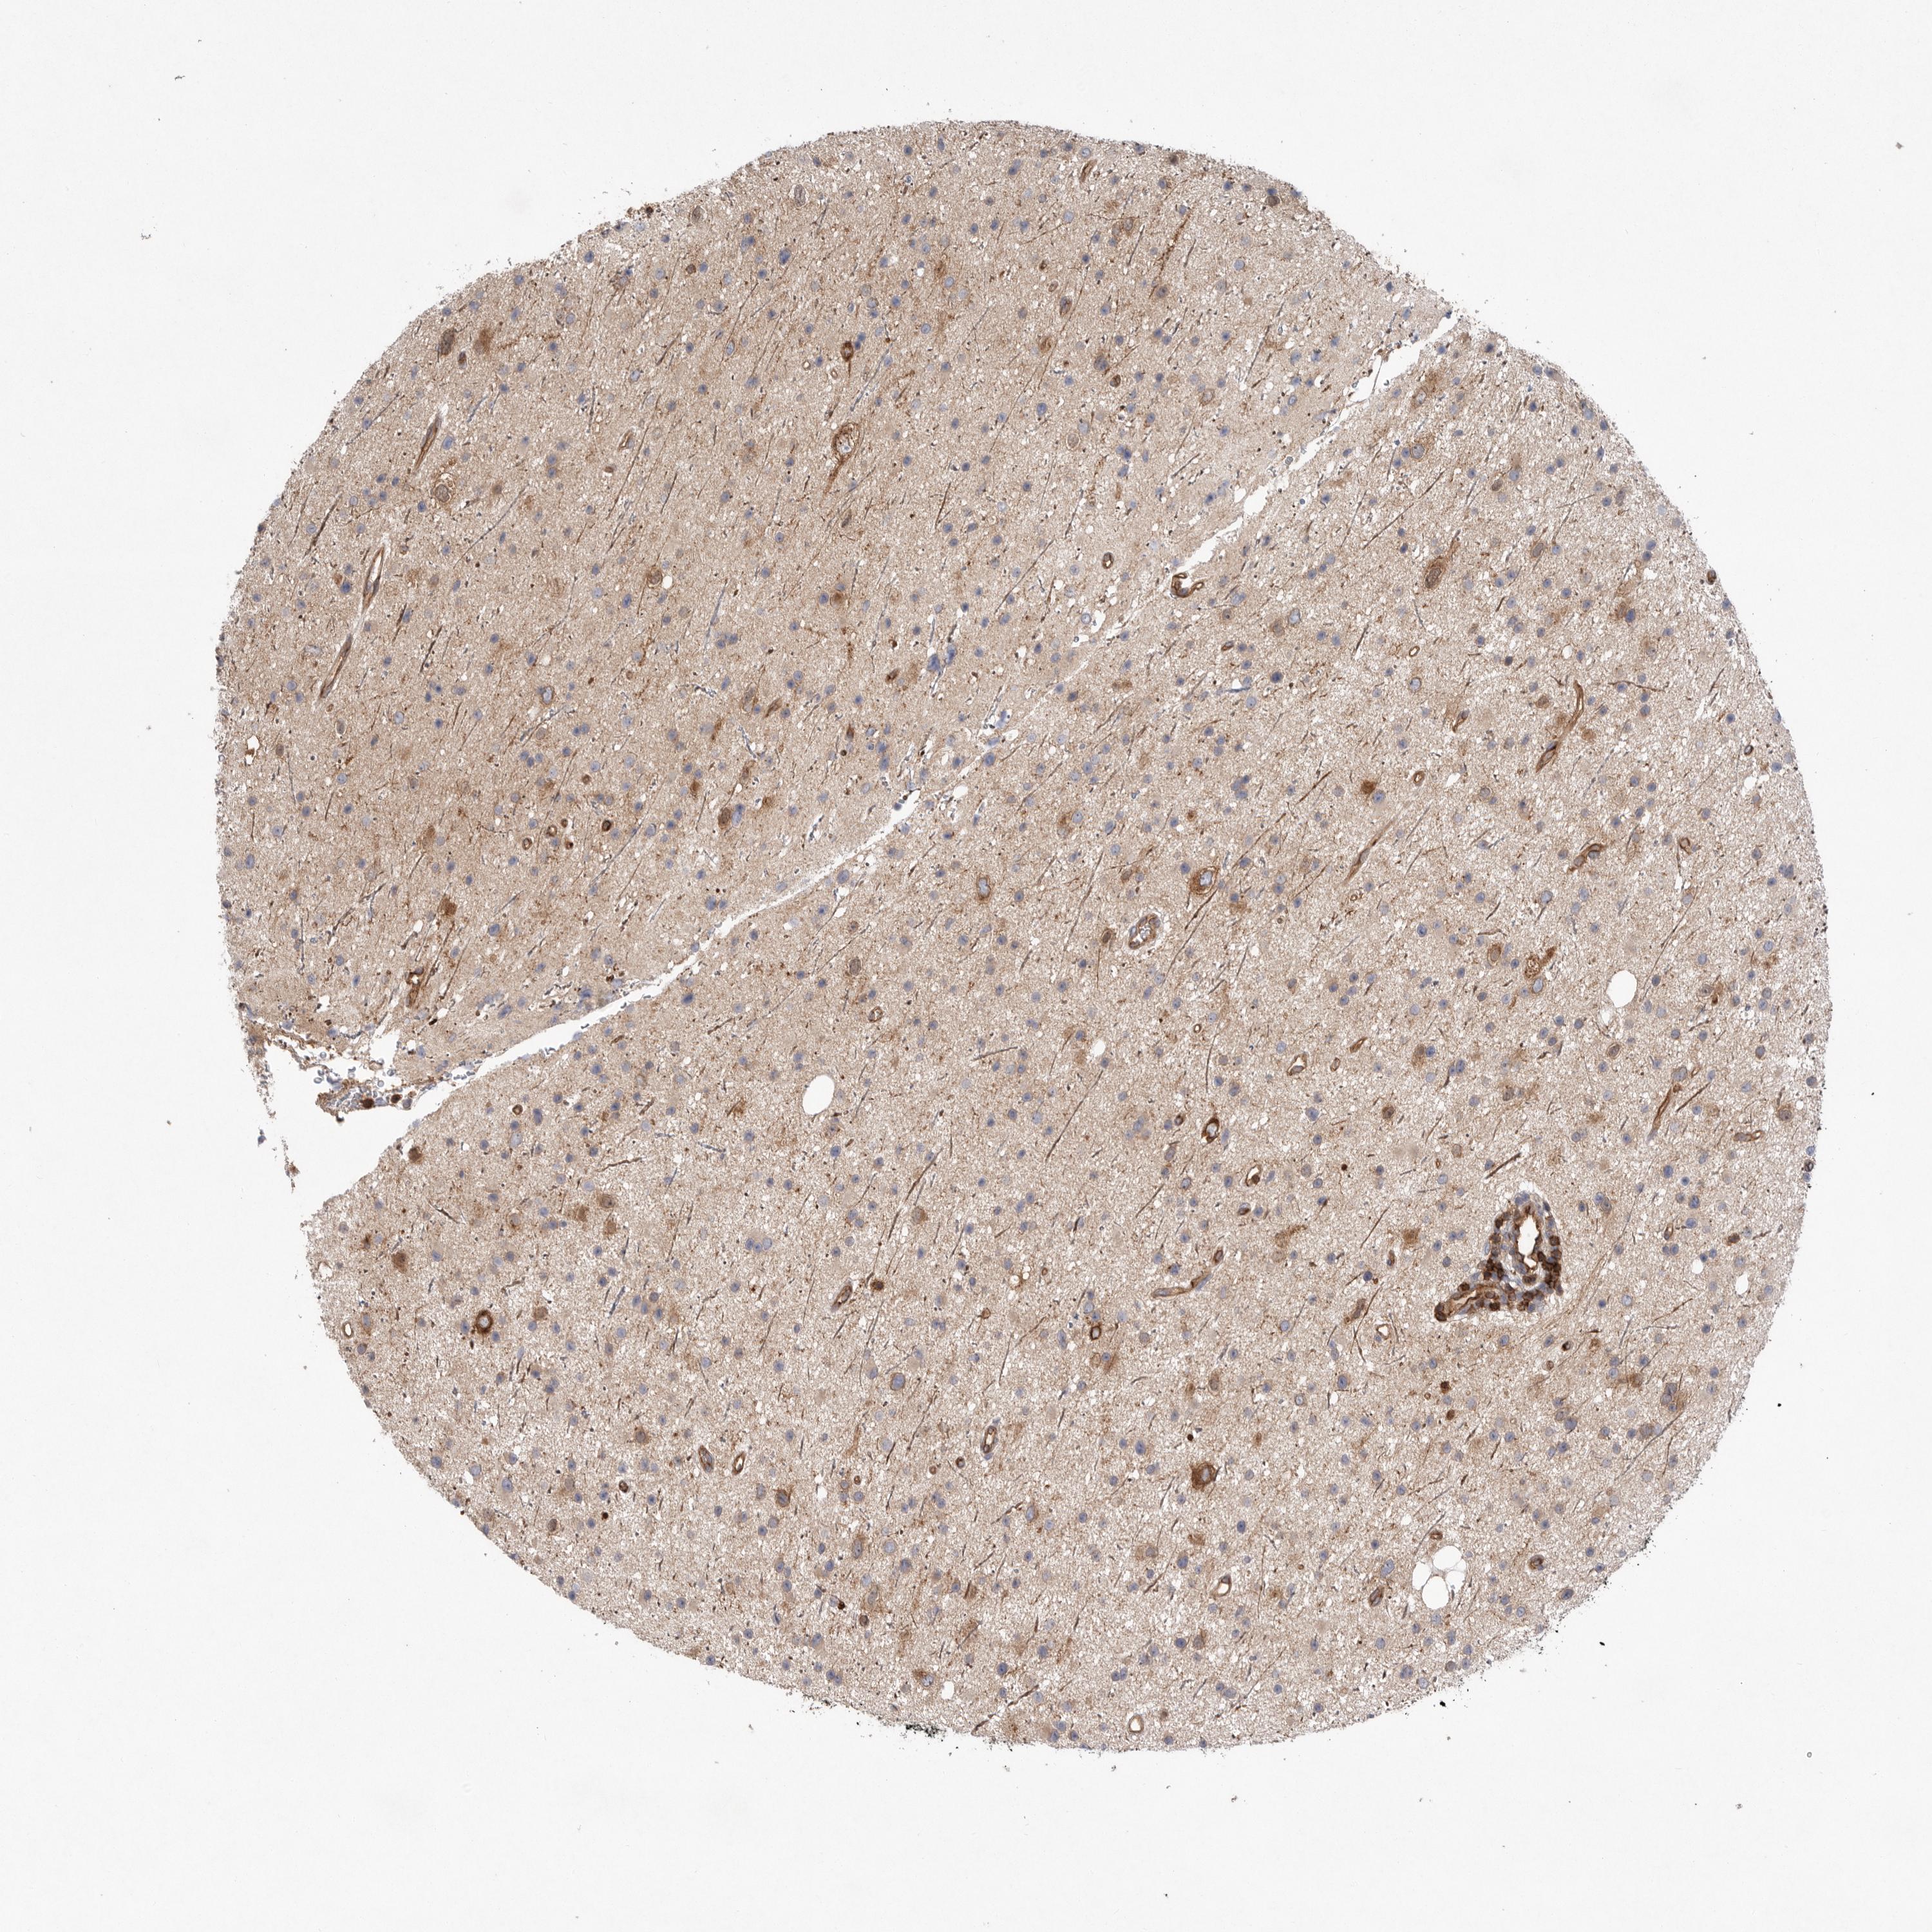

GLIOMA - Protein expressioni

A mouse-over function shows sample information and annotation data. Click on an image to view it in a full screen mode. Samples can be filtered based on level of antibody staining by selecting one or several of the following categories: high, medium, low and not detected. The assay and annotation is described here.

Note that samples used for immunohistochemistry by the Human Protein Atlas do not correspond to samples in the TCGA dataset.

Antibody stainingi

Antibody staining in the annotated cell types in the current human tissue is reported as not detected, low, medium, or high, based on conventional immunohistochemistry profiling in selected tissues. This score is based on the combination of the staining intensity and fraction of stained cells.

Each image is clickable and will lead to virtual microscopy that enables deeper exploration of all samples and also displays staining intensity scores, fraction scores and subcellular localization as well as patient and tissue information for each sample.

Antibody HPA026294

Antibody HPA053709

Staining

High

Medium

Low

Not detected

Intensity

Strong

Moderate

Weak

Negative

Quantity

>75%

75%-25%

<25%

None

Location

Nuclear

Cytoplasmic/membranous

Cytoplasmic/membranous,nuclear

Glioma, malignant, High grade

Glioma, malignant, Low grade

Glioblastoma, NOS